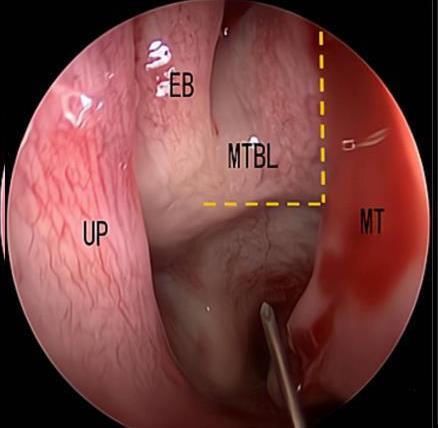

• 内镜下经中鼻甲基板入路四步程序化开放蝶窦的疗效分析

摘要:目的 探究经中鼻甲基板入路的手术技巧及临床效果,旨在系统评估一种兼具良好手术视野和微创性的蝶窦开放径路。方法 回顾性分析2019年9月-2023年9月该院收治的35例孤立性蝶窦病变或单侧蝶窦伴毗邻筛窦受累患者的临床资料,均经中鼻甲基板入路的“四步”程序化操作开放蝶窦。观察手术相关情况和并发症发生情况;采用视觉模拟评分法(VAS)评分,评估头痛和流涕等症状改善情况;采用改良隆德-肯尼迪(MLK)评分,评价术腔恢复状况。结果 所有患者术中保留钩突、中鼻甲和筛泡,26例(74.3%)保留上鼻甲;所有患者均达到临床治愈标准,表现为:术腔引流通畅,黏膜完全上皮化,以及蝶窦开口维持良好开放状态。术后病理显示:蝶窦霉菌病19例(54.3%),蝶窦息肉7例(20.0%),蝶窦黏膜慢性炎症9例(25.7%)。所有患者均未发生严重并发症,仅1例(2.9%)于术后12 d出现中鼻甲创面渗血,经电凝止血后治愈。头痛VAS评分由术前的(4.71±1.66)分,降至术后的(0.83±0.39)分,手术前后比较,差异有统计学意义(t = 13.71,P < 0.01);流涕VAS评分由术前的4.00(0.00,6.00)分,降至术后的0.00(0.00,1.00)分,手术前后比较,差异有统计学意义(Z = -4.47,P < 0.01);手术前后嗅觉减退VAS评分比较,差异无统计学意义(P > 0.05)。MLK评分由术前的4.50(2.00,4.00)分降至1.00(0.00,1.00)分,手术前后比较,差异有统计学意义(Z = -5.20,P < 0.01)。结论 经中鼻甲基板入路蝶窦开放术,严格遵循鼻窦解剖层次,在最大限度地保留鼻腔生理结构的前提下,可获得理想的术野暴露。该术式对于局限于蝶窦及后组筛窦的病变,具有确切的临床疗效。值得应用于临床。